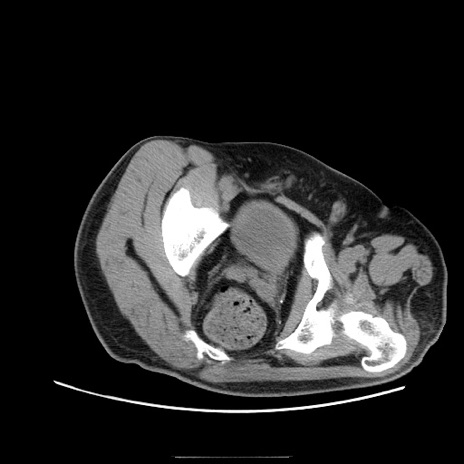

症例22(横断像)

【症例】50歳代男性

【主訴】腹痛

【現病歴】AVMからの被殻出血のため回復期リハ病棟入院中。 本日午後3時頃急に下腹部痛が出現した。

【既往歴】AVM、被殻出血、虫垂炎、高血圧

【身体所見】意識晴明、左半身不全麻痺、会話の理解は良好、36.5°C、腹部:膨隆、全体に板状硬、下腹部正中に圧痛点あり、反跳痛-、筋性防御不明、右下腹部にope scar

【データ】WBC 9400、CRP 0.06